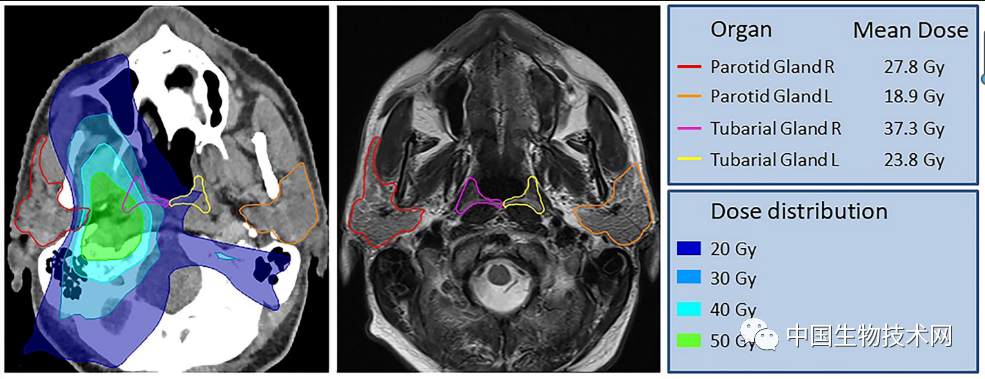

近日 , 发表在《Radiotherapy and Oncology(放疗与肿瘤)》上的一项研究中 , 荷兰癌症研究所领导的研究团队有一个解剖学上的新发现:人体内有一对先前被忽视且与临床相关的“未知实体” , 在接受放疗的患者中保留它们可能会为其提供改善生活质量的机会 。

这个“未知实体”是该团队在对100例前列腺癌或尿道腺癌患者进行回顾性队列检查 , 以评估PSMA PET/CT(前列腺特异性膜抗原正电子发射型计算机断层显像)阳性区域的存在和形态时偶然发现的 。 与放射性葡萄糖注射液搭配使用时 , 该诊断工具可以突出显示体内肿瘤 。

研究人员发现的这个完全不同的腺体 , 位于鼻咽后部 , 它潜伏了相当长的时间 , 可以说是经被科学家们忽略了几个世纪 。

该研究通讯作者、荷兰癌症研究所的放射肿瘤学家Wouter Vogel解释说:“人有三大唾液腺(腮腺、下颌下腺和舌下腺) , 但新发现的不是在那里 。 据我们所知 , 鼻咽中仅有的唾液腺或粘液腺在显微镜下很小 , 多达1000个腺体均匀分布在整个粘膜上 。 所以 , 想象一下 , 当我们发现这些时有多惊讶吧 。 ”

Vogel团队新发现的要大得多 , 它显示出似乎是先前被忽视的一对腺体 , 表面上看是第四大主要唾液腺 , 位于鼻咽后部、上颚上方 , 靠近人类头部的中心 。

该研究第一作者 , 阿姆斯特丹大学的口腔外科医生Matthijs Valstar说:“这两个新发现的区域也具有唾液腺的其他特征 。 根据它们的解剖位置(在咽鼓管上方) , 我们称之为‘管状腺’(tubarial glands) 。 ”

此外 , 使用前瞻性收集的723例头颈部癌症患者队列的临床数据 , 研究人员回顾性研究了放疗对流涎和吞咽的影响 。 结果表明 , 放射线输送至“管状腺”后会给患者带来更大的并发症 。 因此 , 该研究结果不仅有益于未来的肿瘤学 , 而且似乎支持这个被忽视的神秘“未知实体”的结构确实是唾液腺 。

不过 , 该团队承认 , 还需要对更大、更多样化的人群进行更多的研究来验证他们的发现;但他们说 , 这一发现为癌症患者接受放疗前提供了指导 , 因为唾液腺非常容易受到放疗的损害 。 在接受放疗的患者中保留这些腺体可能会为其提供改善生活质量的机会 。